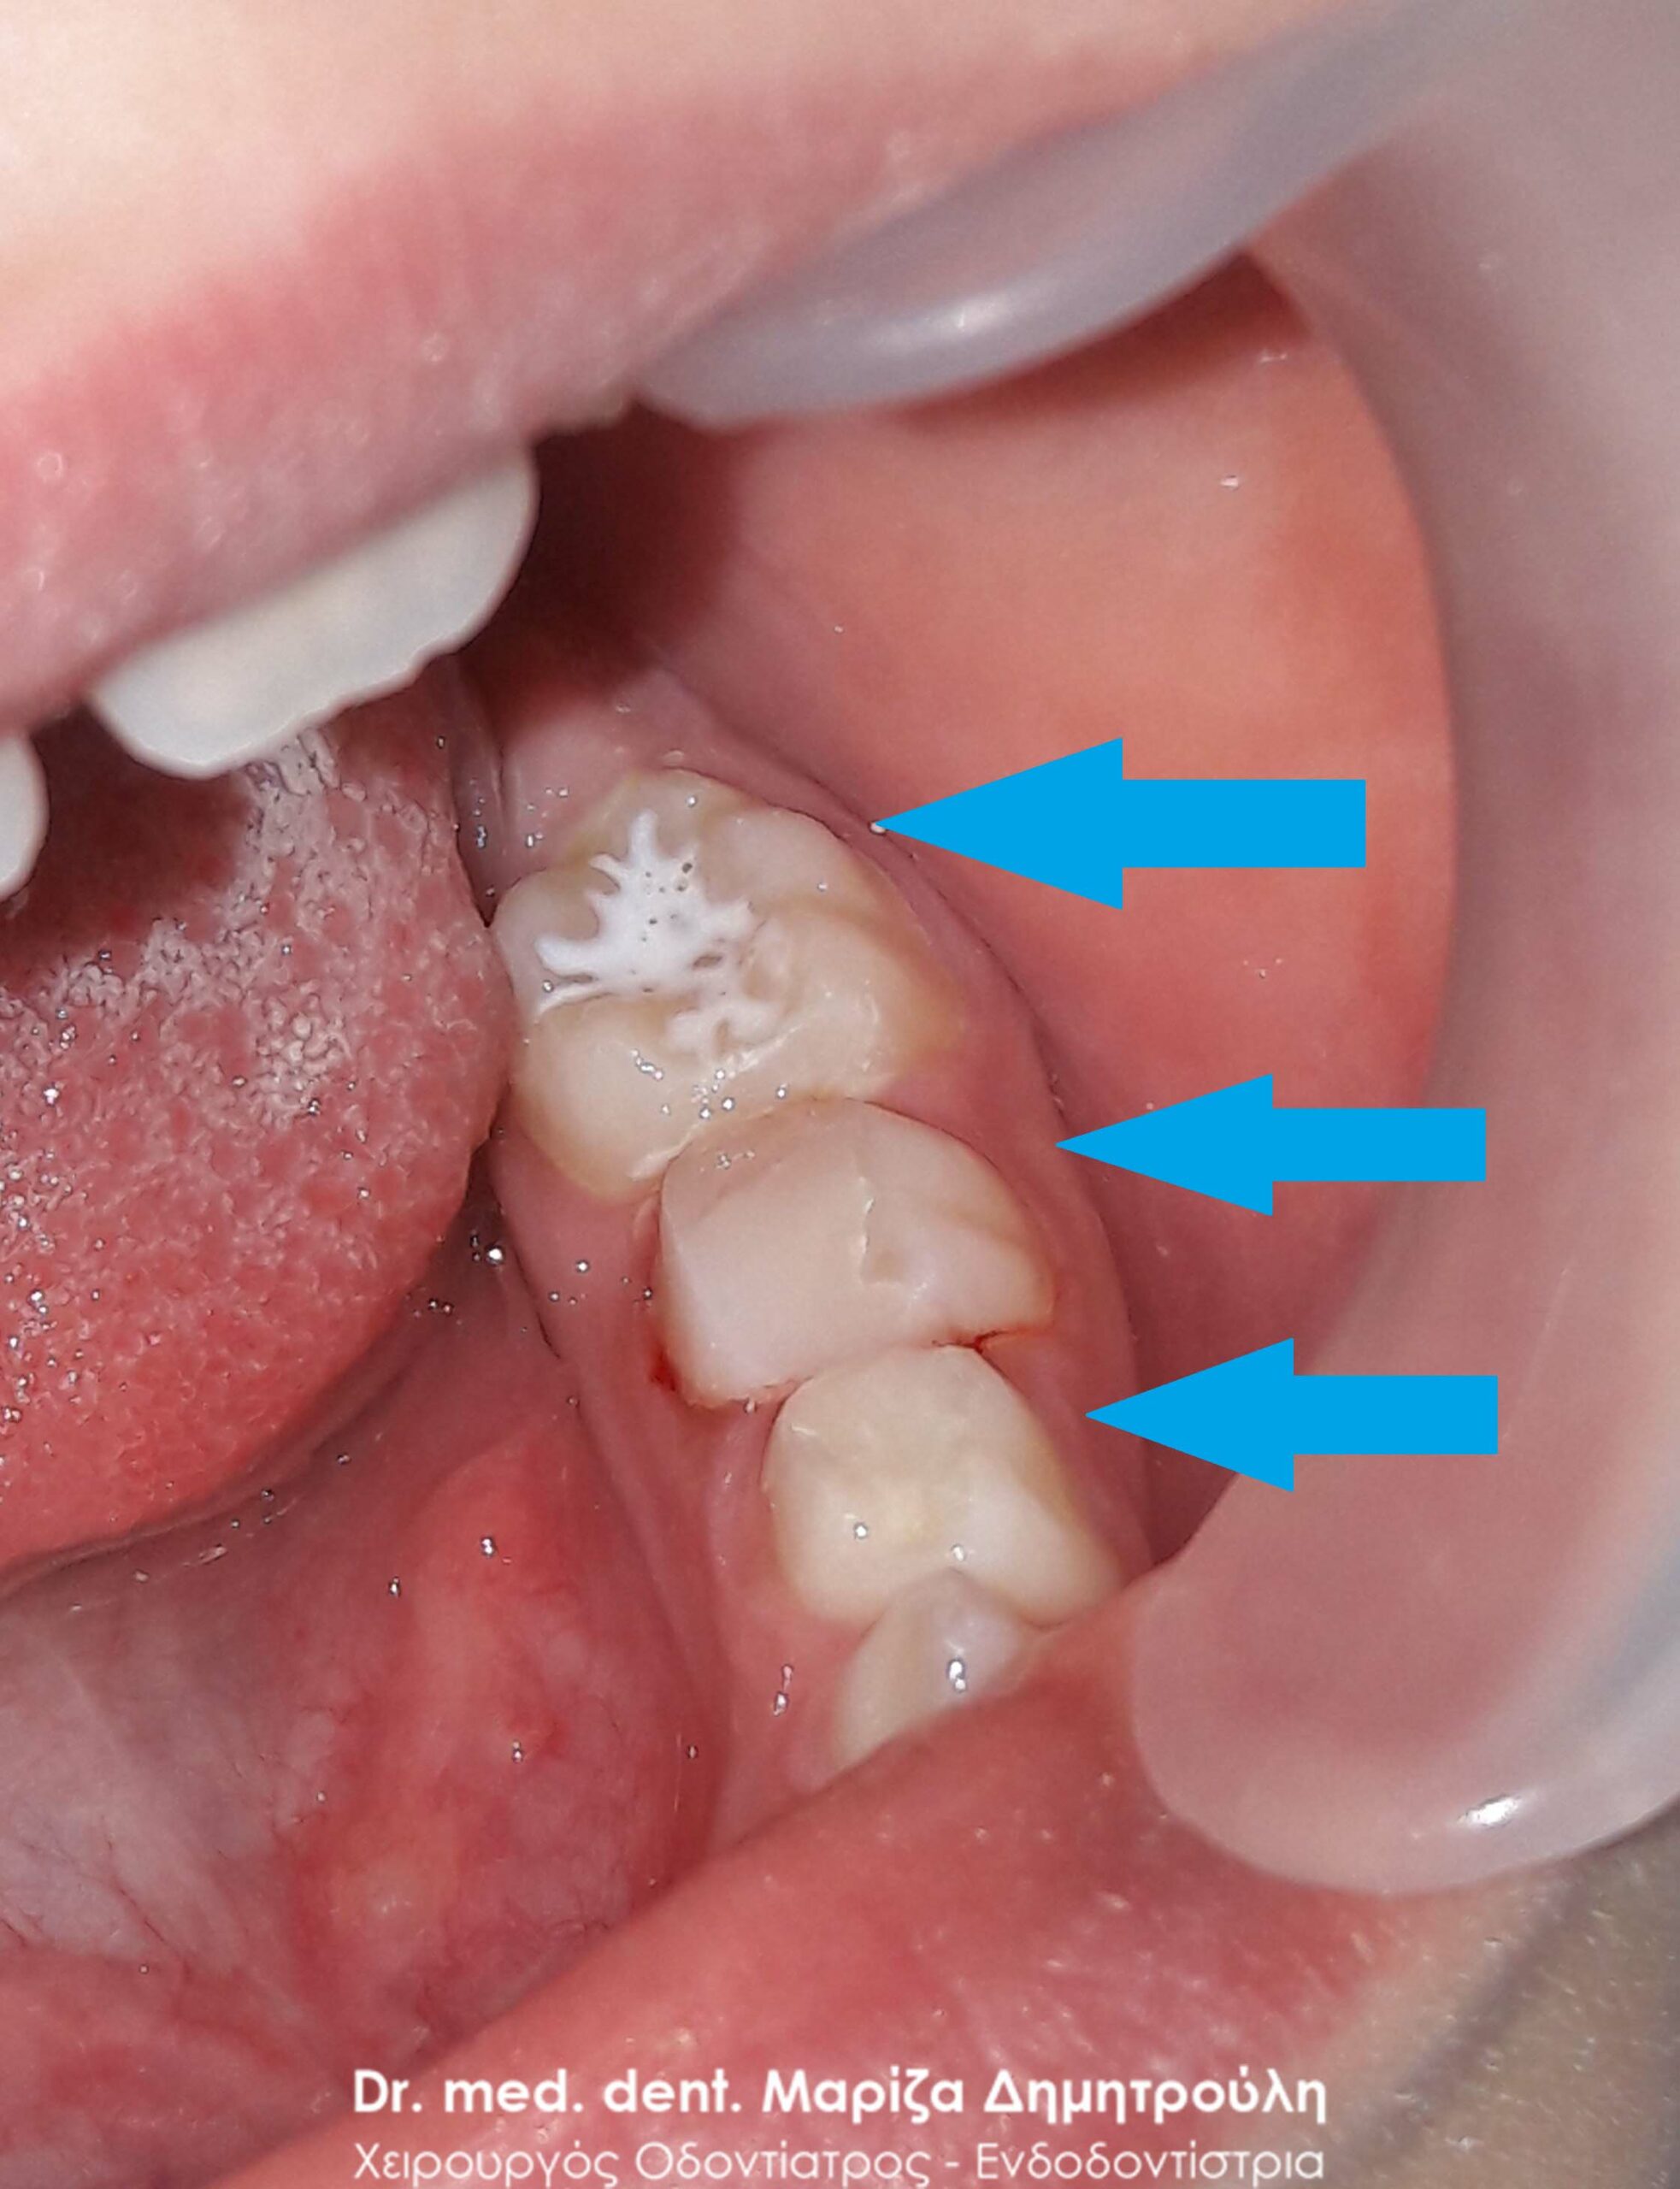

Dental filling of primary tooth

BEFORE